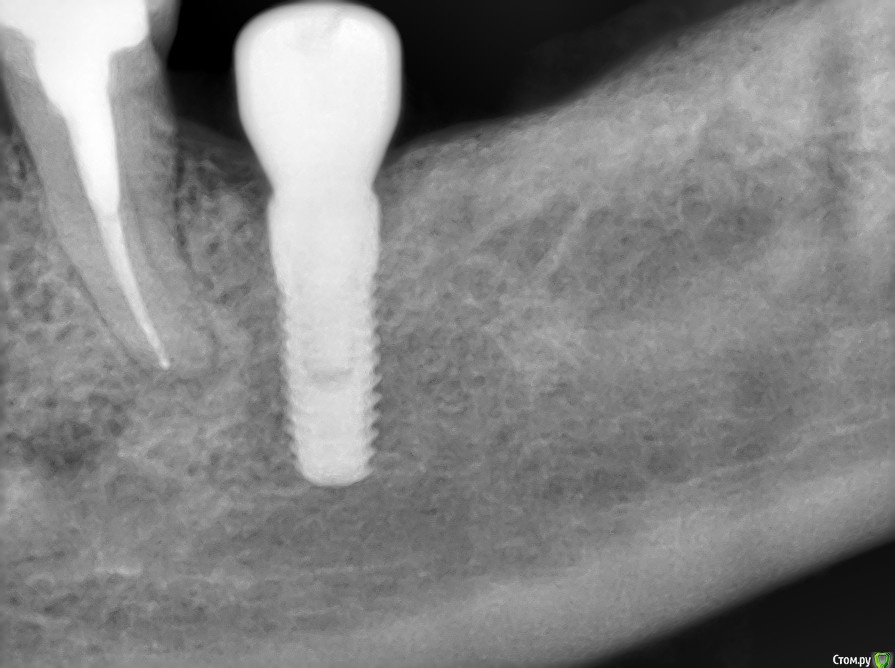

kriokov Опубликовано 7 сентября, 2016 Автор Поделиться Опубликовано 7 сентября, 2016 торк проверю - отпишусь торк 40, все штатно. Открывал без изысков. Крестально разрез, фдм, 2 шва унифлексом. Снимки свежие. 1 Ссылка на комментарий